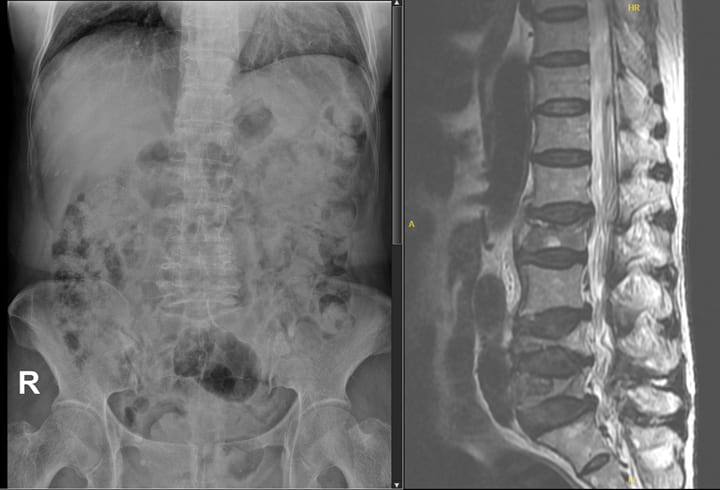

Lumbar X-ray, MRI Lumbar and blood tests

- Lumbar X-ray: Reduced height of L2, L4 and L5 vertebrae

- MRI: Biconcave compression fractures at L2, L4 and L5 vertebrae

- Interpretation: Osteoporotic fracture of L2, L4 and L5